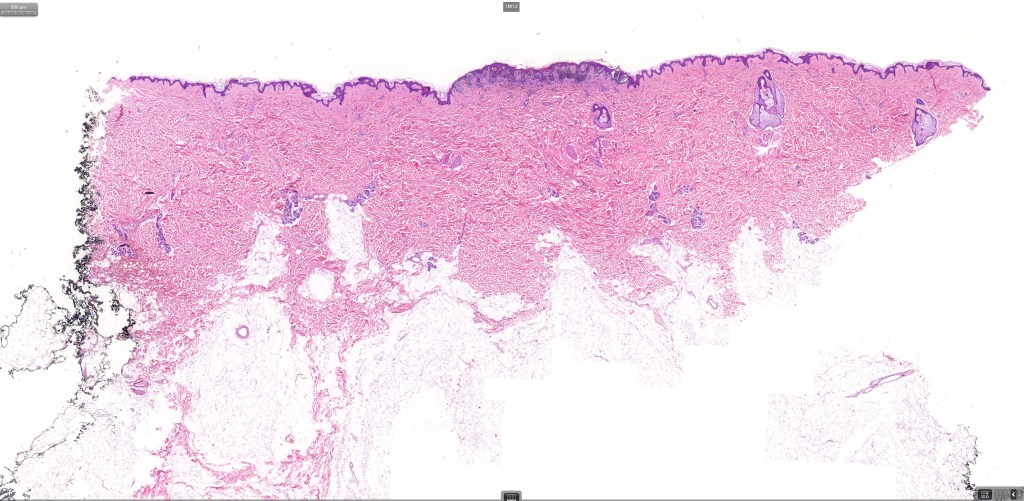

•Variant of Spitz nevus, readily identifiable at scanning magnification in the majority of cases

•Symmetrical and circumscribed with a characteristically flat lower border

•Junctional or compound

•Acanthosis & hyperkeratosis